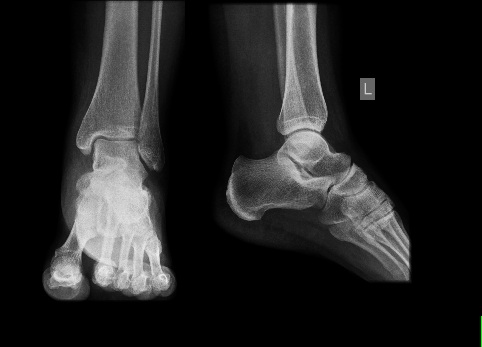

Nie obyło się bez wizyty w SOR, gdyż nogę wlokłam dosłownie za sobą. Szybko zrobiła się fioletowa i spuchła jak bania. Poddano mnie badaniu lekarskiemu (lekarz macał i macał moją kostkę - przyjemne to to nie było), potem wysłał mnie na RTG. Złamania na szczęście nie było, ale rozpoznano silne stłuczenie okolicy kostki przyśrodkowej lewego stawu skokowego - cokolwiek to znaczy...

Na zdjęciu - RTG mojej nogi...